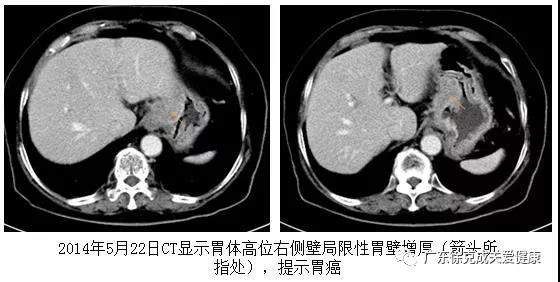

林杨月英,桃园人,86岁。2014年5月21日在台北马偕纪念医院接受胃镜检查,发现贲门下有一隆起肿块,3~4 厘米大小,图像上显示糜烂出血。活检:低分化腺癌。同时作腹部CT,发现贲门下隆起,提示胃新生物。血液肿瘤标记CA19-9 1450单位,比正常升高近40倍。医生建议她接受手术和放化疗。她拒绝了医生的建议。

一个月后,老人吞咽困难改善,8月份复查CA19-9 降低到307单位。医生建议口服希罗达。10月26日复查胃镜,发现原肿瘤已不见,留下白色疤痕。希罗达用至2015年5月,共用9个月,因不良反应而停药。但吸氢继续进行。每半年检查一次CT。近几次CT显示贲门通畅,原先肿瘤征象已经消失。CT等多种检查,未见癌肿转移。